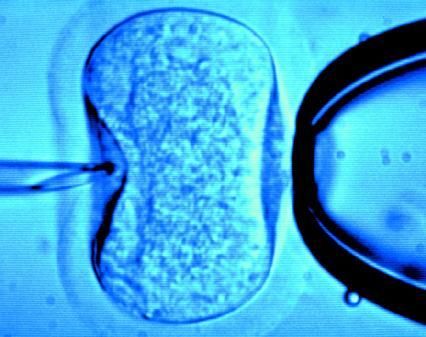

據(jù)英國《每日郵報》1月18日報道,英國一位60歲老婦將成為英國接受試管受精最年長者。這位老婦名叫蘇珊·托勒夫森,是一位退休教師,到今年10月她就滿60歲了。2008年,蘇珊曾去俄羅斯接受試管受精,在英國生下了她的第一個孩子。

倫敦哈利街的私人診所是英國試管嬰兒手術成功率較高的醫(yī)院之一,醫(yī)生們在上周一同意幫助蘇珊·托勒夫森進行第二次人工受孕。通常情況下,私人診所只在特殊情況下給50歲以上的婦女進行試管受精,例如,患者仍然有月經周期。這件事引起了絕經后婦女是否有生育權利的倫理大討論,現(xiàn)在要求提高生育治療年齡上限的呼聲越來越高。

現(xiàn)在,蘇珊·托勒夫森一家人很幸福,丈夫尼克·邁耶是一位公司經理,比她小11歲,他們的女兒今年2歲。專家表示,蘇珊很健康,她的女兒如果能有一個兄弟姐妹會更好,于是蘇珊想再次接受試管受精!缎瞧谌锗]報》獲悉,倫敦哈利街私人婦女診所的高級工作人員已經同意為蘇珊做試管受精,還決定幫助另一位57歲的老婦受孕。(海瀾)